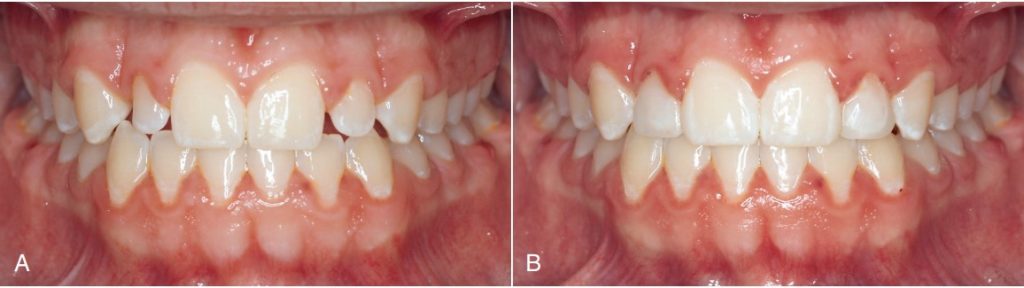

Tiếp theo là đánh giá chất lượng của nướu dính. Độ dày (theo chiều nhai–nướu) và chiều rộng của nướu dính cũng rất quan trọng. Những yếu tố này thường bị bỏ sót và sự tụt nướu có thể xảy ra khi răng bị di về phía ngoài khỏi xương ổ răng. Cần lưu ý tụt nướu cũng có thể đã tồn tại trước khi bắt đầu điều trị (hình 1-32).

Trong lần khám ban đầu, bác sĩ cần lưu ý tình trạng chen chúc giữa các răng cửa hàm trên có thể đẩy điểm tiếp xúc xuống thấp về phía nướu; vì vậy khi đạt được sự sắp xếp đúng trong giai đoạn đầu của điều trị, điểm tiếp xúc có thể dịch chuyển lên phía rìa cắn, và hậu quả là tam giác đen có thể xuất hiện (Hình 1-37).